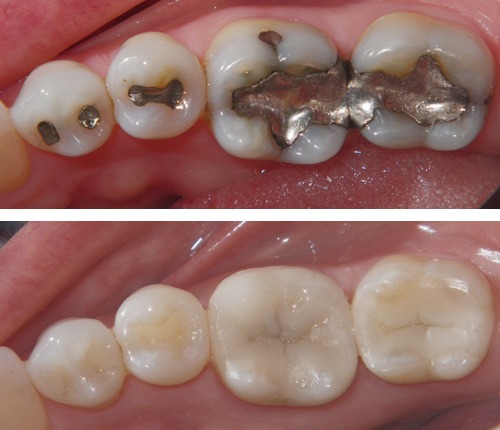

TOOTH COLOUR FILLINGS

DEEP DENTAL CARIES MANAGEMENT

Used to restore cavities, fractures, or seal post-RCT teeth.

Advantages: